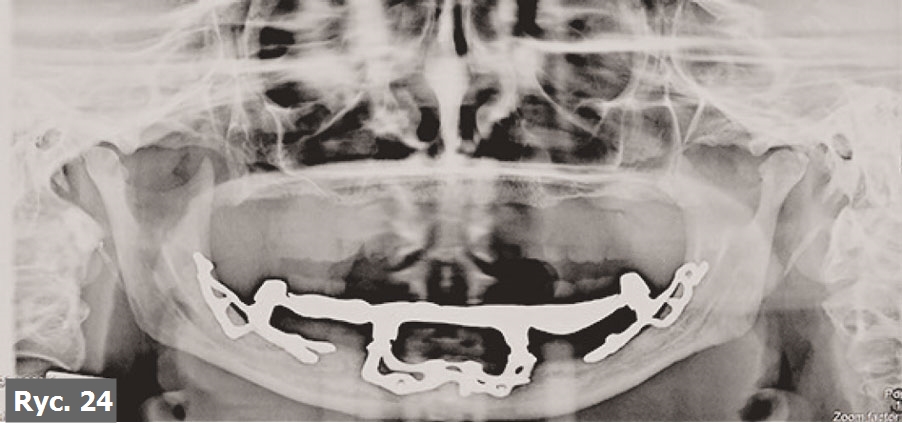

Pacjentkę poinformowano, że jedyną metodą leczenia, która jej pozostała, jest zastosowanie wszczepu podokostnowego. Skierowano ją do Turynu, do dr. G. Cortese. Po analizie badania TK oraz modelu stereolitograficznego doktor G. Cortese zdecydował, że najbardziej odpowiednim wszczepem, który rozwiąże problemy pacjentki, będzie trzyczęściowy implant podokostnowy Linkowa. Zarówno zabieg chirurgiczny, jak i wykonanie ostatecznego uzupełnienia protetycznego przebiegły bez większych problemów (ryc. 23, 24).